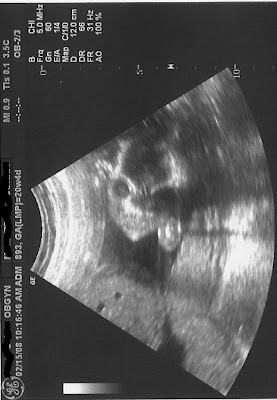

Todas as imagens dos ultra sons são reais e até onde sabemos os bebes nasceram normais.